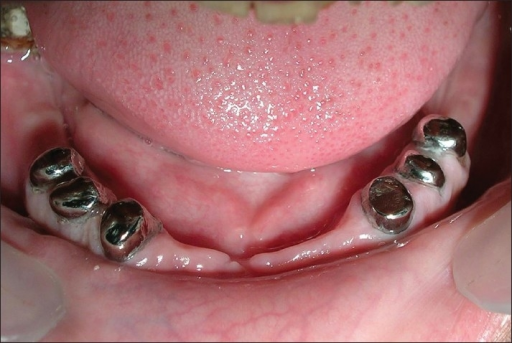

Descripción: Clinical examination revealed 7-mm probing depths, circumferentially around a mandibular implant, bleeding on probing, and the presence of exudate and gingival inflammatory edema